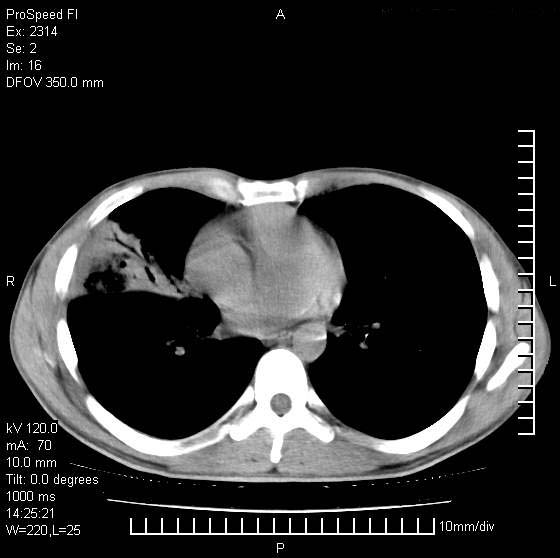

男性,再生障碍性贫血,入院前发热10天,最高40c,右侧胸痛,外院ct示右上,中肺边缘模糊的球性影(就是我现在图中标示的范围),考虑炎症,在我院使用头孢呋辛,洛美沙星10天,高烧消退,自感下午稍有发热,但今天ct示右上,中肺病灶明显扩大,还是考虑炎症,看其中的球型影是否霉菌感染??,是否能排除结核?

肺脓肿,伴双肺播散

支持考虑真菌感染,内部密度低些,且与外壁有分离,不符合肺脓肿表现,但最好有前片对比,

片状高密度影内见空洞影,内可见球形软组织密度影,并有新月征,考虑霉菌感染.